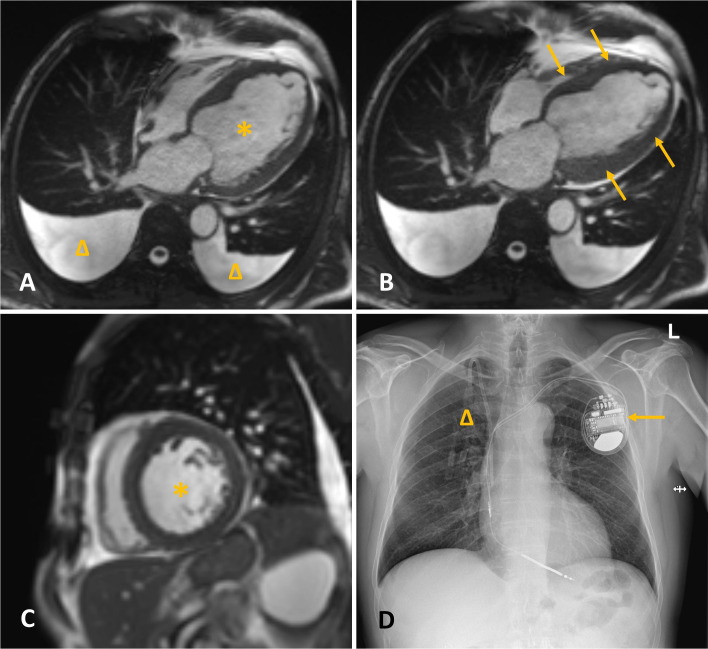

我们报告一例57岁男性患者(美国麻醉师协会IV级)在单侧胸椎旁阻滞(TPVB)和镇静下接受开放胆囊切除术。患者有严重的心力衰竭,射血分数降低了约16%,并植入了皮下植入式心律转复除颤器。通过超声,我们确定了右侧四个水平(从Th6到Th9)的胸椎旁间隙,并每水平给予3.5 mL 0.5%左布比卡因,总共14 mL。应用TPVB 20分钟后,我们证实了从Th5到Th10皮节的感觉阻滞。手术开始10分钟,在肝包膜收回过程中,患者感到一些疼痛(视觉模拟评分为5/10)。静脉注射舒芬太尼10µg,静脉注射异丙酚50 mg镇静镇痛,成功治疗疼痛。手术持续了45分钟,顺利完成。术中持续镇静,我们使用10mg /h雷马唑仑,维持血流动力学稳定。手术后9小时,患者报告VAS疼痛评分为5分,并接受75mg双氯芬酸钠静脉注射,无需进一步镇痛。患者于术后第6天出院。综上所述,TPVB联合雷马唑仑镇静是一种可行的心脏高危患者开腹胆囊切除术麻醉镇痛技术。

We present a case of a 57-year-old male patient (American Society of Anesthesiologists status IV) undergoing open cholecystectomy under unilateral thoracic paravertebral block (TPVB) and sedation. The patient had severe heart failure, a reduced ejection fraction of approximately 16%, and an implanted subcutaneous implantable cardioverter-defibrillator. Using ultrasound, we identified the thoracic (Th) paravertebral spaces on the right side at four levels (from Th6 to Th9) and administered 3.5 mL of 0.5% levobupivacaine per level, for a total of 14 mL. Twenty minutes after TPVB application, we confirmed sensory blockade from the Th5 to Th10 dermatomes. Ten minutes into surgery, during liver capsule retraction, the patient experienced some pain (5/10 on the visual analogue scale, VAS). The pain was successfully treated with rescue analgesia of 10 µg of intravenous (IV) sufentanil and a sedation dose of 50 mg IV propofol. The surgery lasted 45 minutes and was completed uneventfully. For continued intraoperative sedation, we used 10 mg/h remimazolam, maintaining hemodynamic stability. Nine hours after surgery, the patient reported a VAS pain score of 5 and received 75 mg of IV diclofenac sodium, with no further analgesia required. The patient was discharged on postoperative day six. In conclusion, the application of TPVB combined with remimazolam sedation could present a feasible anesthetic and analgesic technique for open cholecystectomy in high-risk cardiac patients.